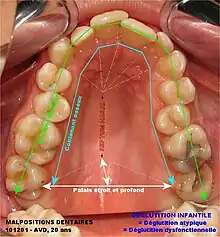

Fig.6. Déglutition salivaire infantile, atypique (adulte) et dysfonctionnelle. L'étalement horizontal de la langue ne stimule pas le développement du palais. Chez l'adulte, il en résulte un palais étroit et profond, associé à un encombrement dentaire (« contenu »).

La déglutition infantile, ou déglutition primaire, caractérise la fonction linguale chez tous les nourrissons et les enfants : ce réflexe naît au quatrième mois de la grossesse (réflexe inné) et elle se manifeste par une langue qui s'étale horizontalement entre les deux maxillaires, ou « interposition linguale ». Chez plus de 75 % des adultes, un étalement horizontal persistant de la langue devient une dysfonction : c'est la déglutition atypique, ou déglutition dysfonctionnelle. Les logopèdes (Belgique) / orthophonistes (France) tentent, tant bien que mal, de corriger cette interposition linguale via des exercices volontaires, ou myothérapie fonctionnelle (MTF). Mais, face à l'automatisme inné des réflexes de la déglutition salivaire, l'efficacité de la MTF reste sujette à caution. Une déglutition atypique favorise la respiration buccale, accompagnée d'une étroitesse des mâchoires et d'un manque de place pour aligner toutes les dents permanentes. Ceci peut conduire aux malocclusions ou aux dysfonctions des mâchoires : SADAM, DAM, STM, etc.

Via les pressions de la langue sur les parois palatines osseuses (procès alvéolaire), la déglutition salivaire physiologique, dite « en dents serrées » (A. Jeanmonod) est répétée 1 500 à 2 000 fois par jour : c'est le principal moteur de la croissance du massif facial osseux. Le rôle premier de la déglutition est d’éliminer le bol salivaire vers l'œsophage, soit une sécrétion quotidienne totale de 1 500 millilitres. Par an, cela représente un peu moins d'une demi-tonne de liquide. La déglutition salivaire est le travail le plus contraignant de la cavité buccale. Dans les conditions physiologiques de la déglutition salivaire, la langue s'élève dans le palais et produit des pressions sur les procès alvéolaires et sur la voûte palatine. La déglutition salivaire contribue à la croissance osseuse et au développement du palais, des fosses nasales et du sinus maxillaires. La croissance de l'os alvéolaire permet un alignement adéquat des dents permanentes. Le développement des fosses nasales permet une respiration nasale chez l'adulte et une bonne ventilation des sinus maxillaires. La fonction linguale a donc un rôle majeur dans le développement et la croissance de l'être humain avant d'aboutir à l'âge adulte.